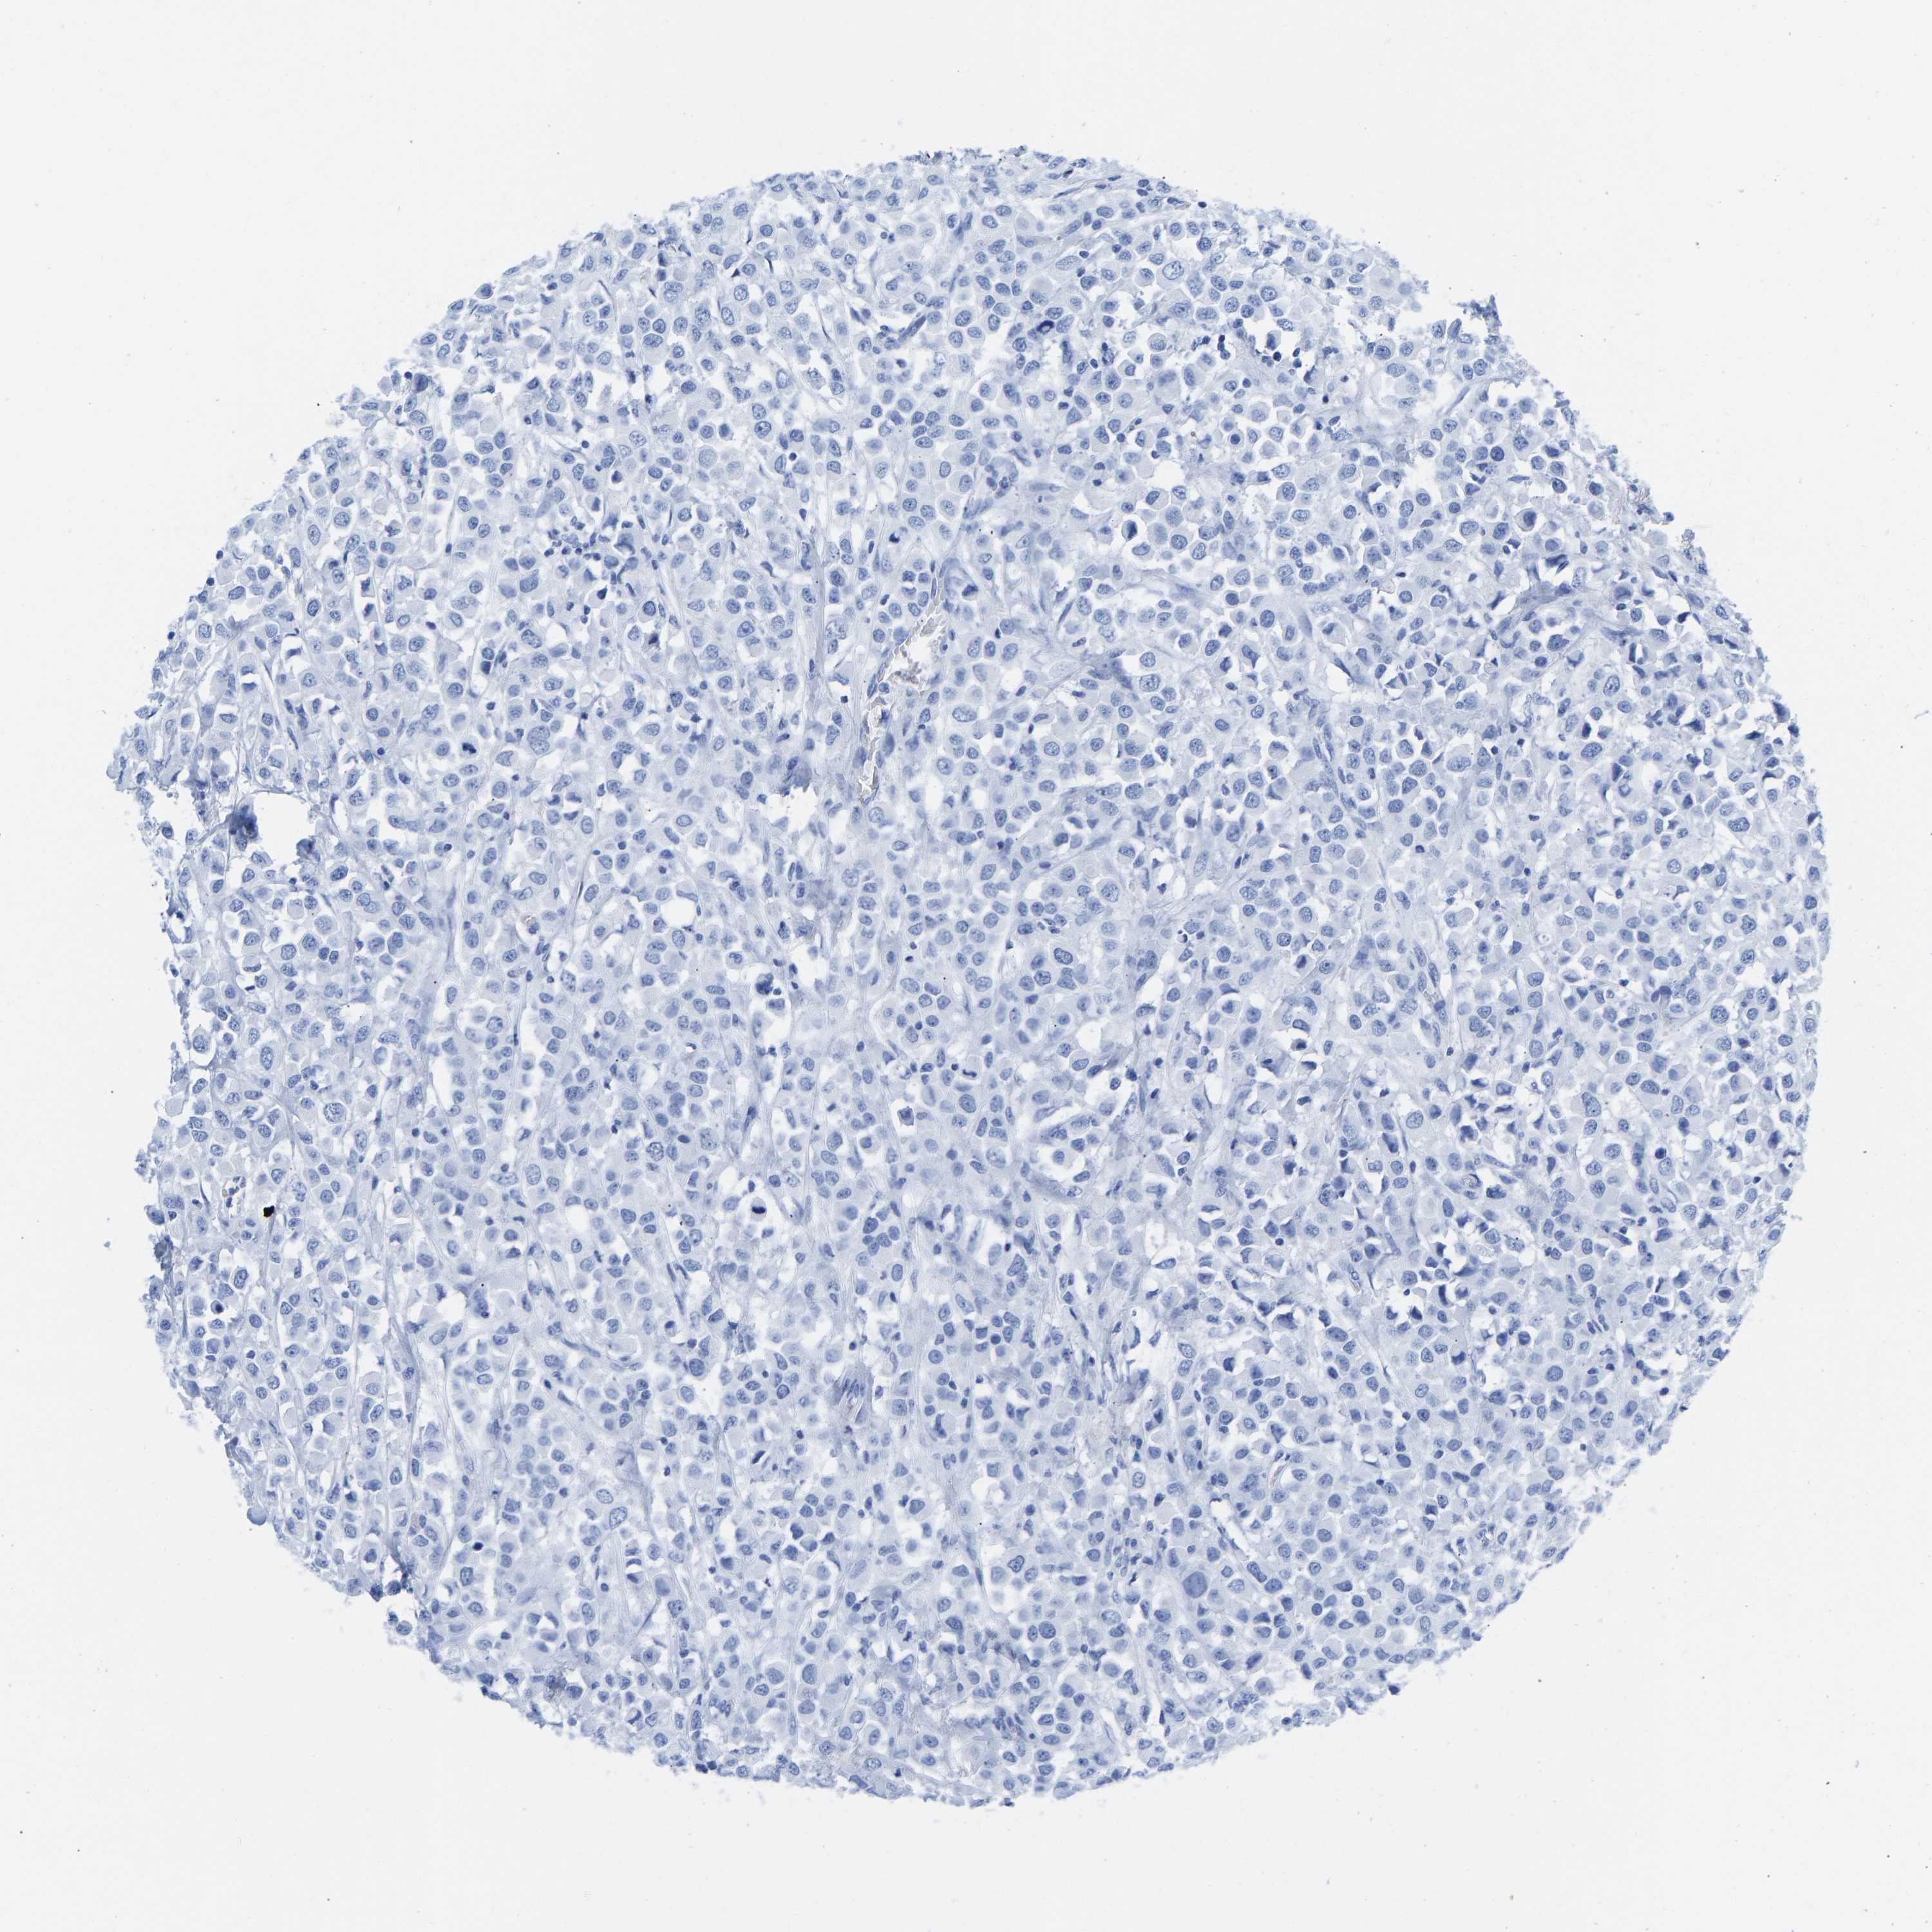

CANCER BREAST CANCER Show tissue menu

BRCA TCGA BRCA VALIDATION PROTEIN EXPRESSION